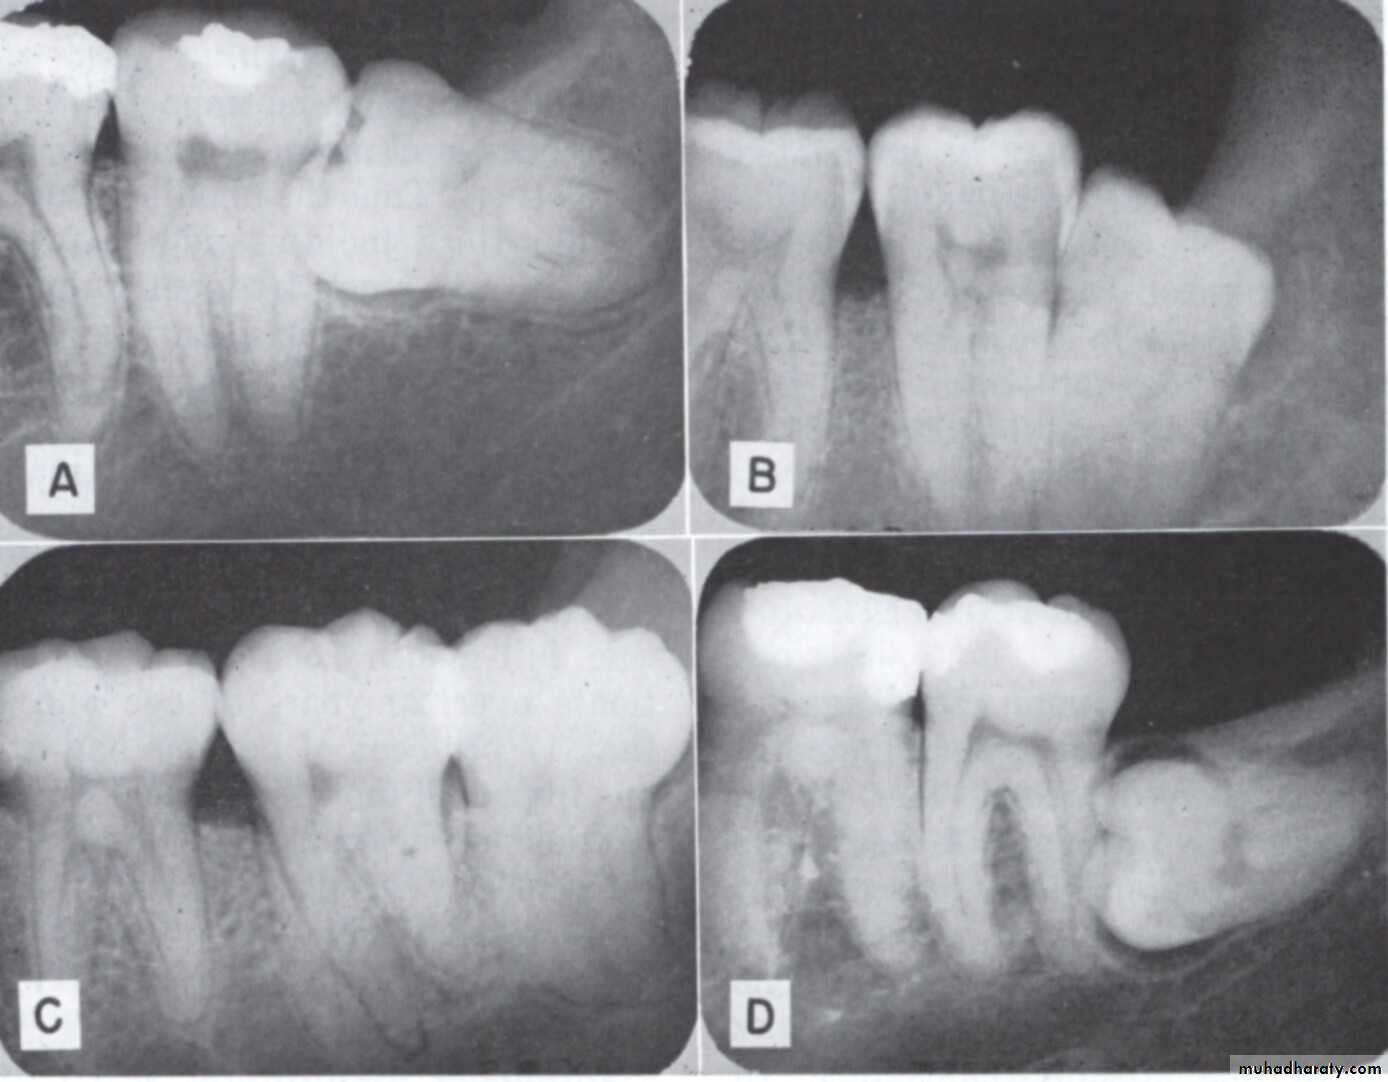

1- Pell and Gregory classification according to the depth or according to the relation of the impacted tooth to the occlusal plane of the lower second molar

2- Pell and Gregory classification according to the relation ship of the lower second molar to the anterior border of the ramus

according to the depth:

Level A the highest point of the occlusal surface of the impacted tooth lie with or above the occlusal surface of the second molarLevel B the highest point of the impacted tooth lie below the occlusal surface but above the cervical surface of the lower second molar

Level C the highest point of the occlusal surface o f the impacted tooth lie below the cervical line of the lower second molar .

Relation of the impacted tooth to the anterior border of the ramus

Class 1 : the space between the lower second molar and the anterior border of the ramus is sufficient to accommodate the mesio distal dimension of the crown of the impacted lower third molarClass 2 : the space between the lower second molar and the ramus is insufficient to accommodate the crown of the impacted tooth .so part of it in the body and the other part lie in the ramus .

Class 3 the anterior border of the ramus lie near the distal surface of the lower second molar ,so ,the whole impacted tooth lie within the ramus .

The difficulty index (Pederson sclae):Angulations Mesioangular 1 , horizontal or transverse 2, Vertical 3, disto angular 4.

Depth : level A value 1 ,level B value 2 ,level C value 3

Ramus relation ship cl 1 value 1, cl 2 value 2 , cl 3 value 3.